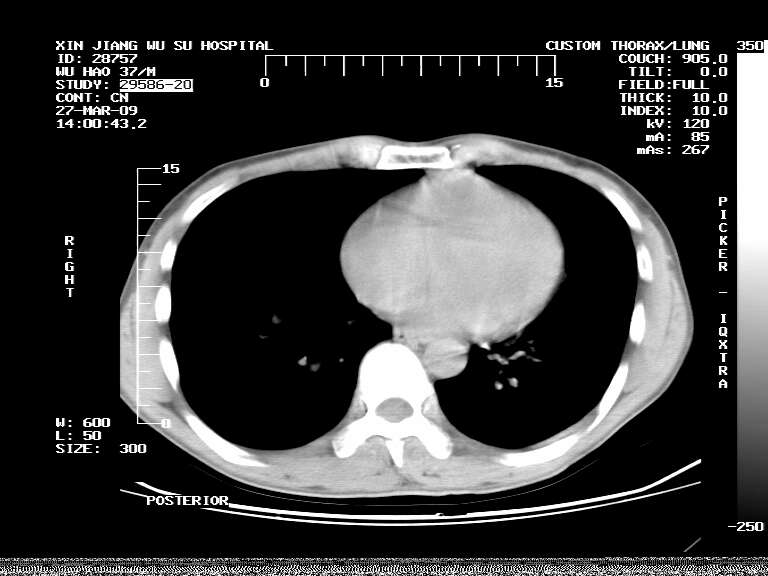

男,37岁,体检胸透发现阴影。

患者体检发现 无症状 左肺下叶占位,边缘模糊,可见血管聚束、分叶、胸膜牵拉,增强呈不均匀性强化。 首先考虑左肺下叶周围型肺癌,建议穿刺活检。

左肺下叶见一结节病变,边缘欠清不光滑,与胸膜粘连且胸膜局限性增厚,注药后呈环形强化,动脉期壁呈明显点环状强化,静脉期壁强化减低,中心密度低无强化,灶周无明显的卫星灶和水肿区(晕征)---考虑周围性肺癌,不除外感染性病变,建议穿刺活检。

左肺下叶软组织病灶,密度较高,内见点状钙化,其周围见子灶,邻近胸膜扁平样增厚.c+病灶强化明显,中心强化弱.诊断:左肺下叶结核瘤.

周围有卫星灶,胸膜反应不明显,病灶中心有坏死。建议先抗结核治疗后,短期复查

左肺下叶大片实变影,内靠胸膜见不规则更高密度结节灶,边缘强化,相邻胸膜增厚,胸膜下脂肪线存在。考虑炎症,结核可能。